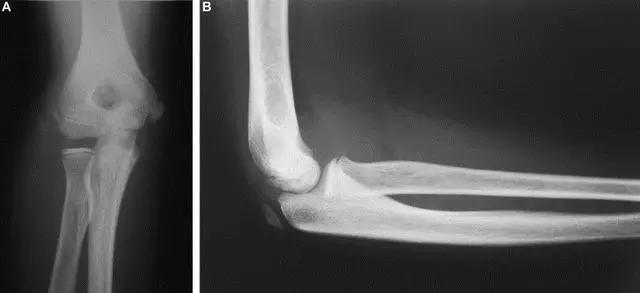

5. Kocher-Lorenz 骨折

单纯肱骨小头骨折。

Kocher-Lorenz 骨折(来源:The often-missed Kocher-Lorenz elbow fracture. Revue de Chirurgie Orthopédique et Traumatologique, Volume 95, Issue 7, November 2009, Pages 658-661)

6. Hahn-steinthal 骨折

全肱骨小头骨折,为一种少见的关节内骨折,多见于成年人。常由于跌倒时手过度伸直或在屈肘时因桡骨小头撞击肱骨小头,并同时有外翻力存在时发病,亦可伴有滑车骨折与内侧副韧带的撕裂。X 线表现为全肱骨头骨折,向上移位。

Hahn-steinthal 骨折 X 片(来源:Hahn-Steinthal fracture: a case report.BioMed central Cases Journal20081:239)

Hahn-steinthal 骨折 CT 片(来源:Hahn-Steinthal fracture: a case report.BioMed central Cases Journal20081:239)